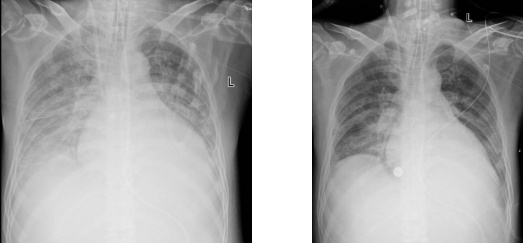

接受治疗后肺部逐渐恢复正常

经过5天的治疗,小刘的“大白肺”基本恢复成正常状态,又过了2天,他成功撤离呼吸机并拔除气管插管,痰培养显示,鲍曼不动杆菌也已经转阴,休养了一个礼拜后,顺利出院了。